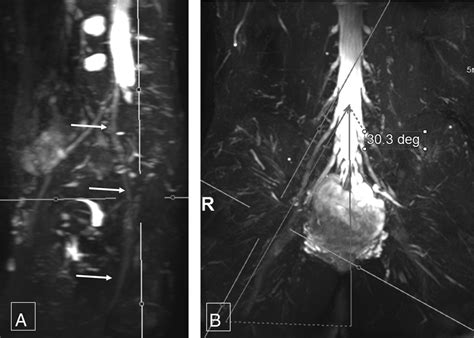

Once the images are acquired, they are analyzed by a radiologist with specialized expertise in musculoskeletal or neuroradiology. The goal is to identify changes in the nerve's appearance. For instance, a healthy nerve typically appears as a thin, uniform structure with a consistent signal. In contrast, an injured or compressed nerve may exhibit:

• Increased signal intensity: Often indicative of edema (swelling) or inflammation within the nerve.

• Nerve enlargement (fascicular thickening): A sign that the nerve is being subjected to chronic pressure or trauma.

• Discontinuity or disruption: Clearly visible in cases of severe trauma or nerve rupture.

• Masses or Lesions: Clear identification of tumor growth within or adjacent to the nerve sheath.